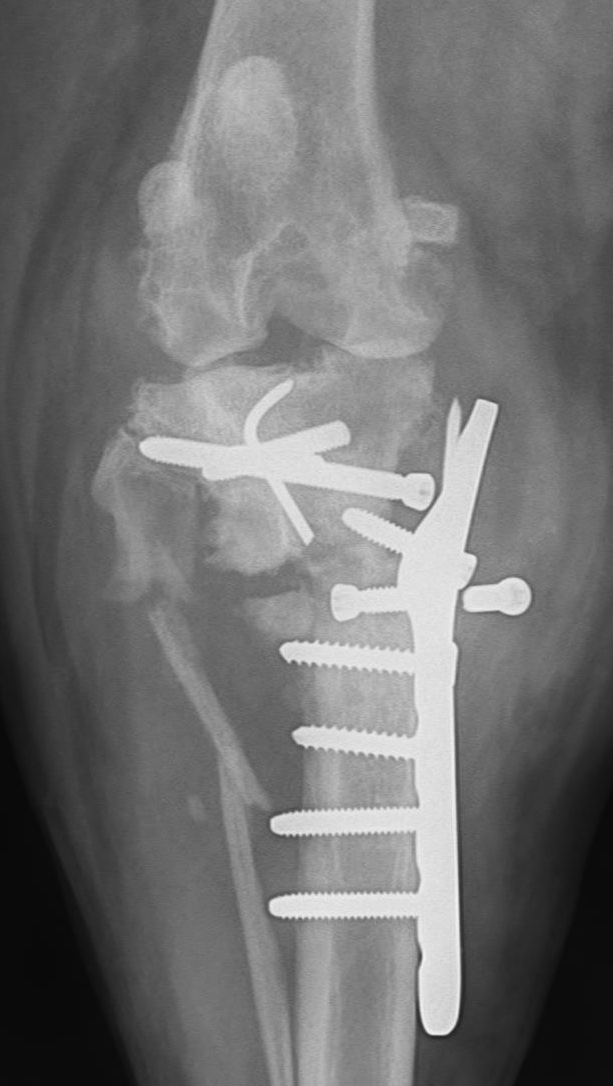

What would you do with this :-0 Our autumn meeting is all about...REVISION SURGERY! 20-22nd Nov in Bristol, full details and booking info shared here v soon :-)

What would you do with this :-0

Our autumn meeting is all about...REVISION SURGERY!

20-22nd Nov in Bristol, full details and booking info shared here v soon :-)